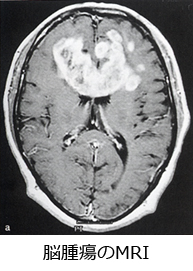

脳腫瘍の診断には、画像診断(特にMRI)が有用です。脳腫瘍の可能性が高ければ、造影MRIが極めて有効です。MRI検査で、ある程度良性か悪性か、またはどこから発生した腫瘍か、さらに腫瘍の組織型まで推測することができます。しかし確定診断には、手術などによる摘出や生検術によって腫瘍組織を採取し、顕微鏡による検査で確定することが必要です。